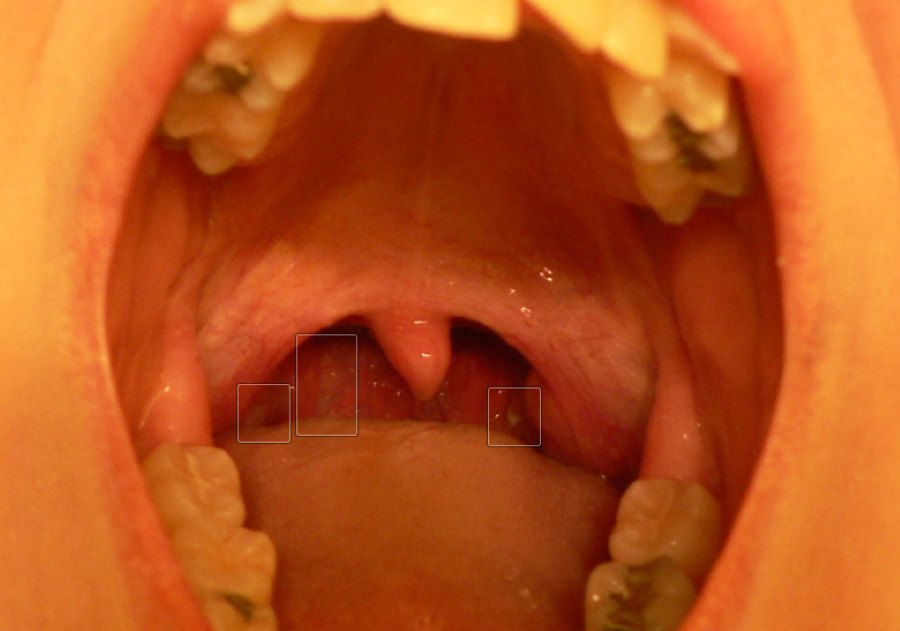

Streptococcal Pharyngitis or strep throat is a Group A Streptococcus bacterial infection characterized by intense throat inflammation, fever, and swollen tonsils, which may accompany white spots.

This is a complication of tonsillitis in which pus collects around the tonsils. It is caused by bacterial infections and results in severe throat pain, fever, and difficulty swallowing. It usually requires surgery and antibiotics.